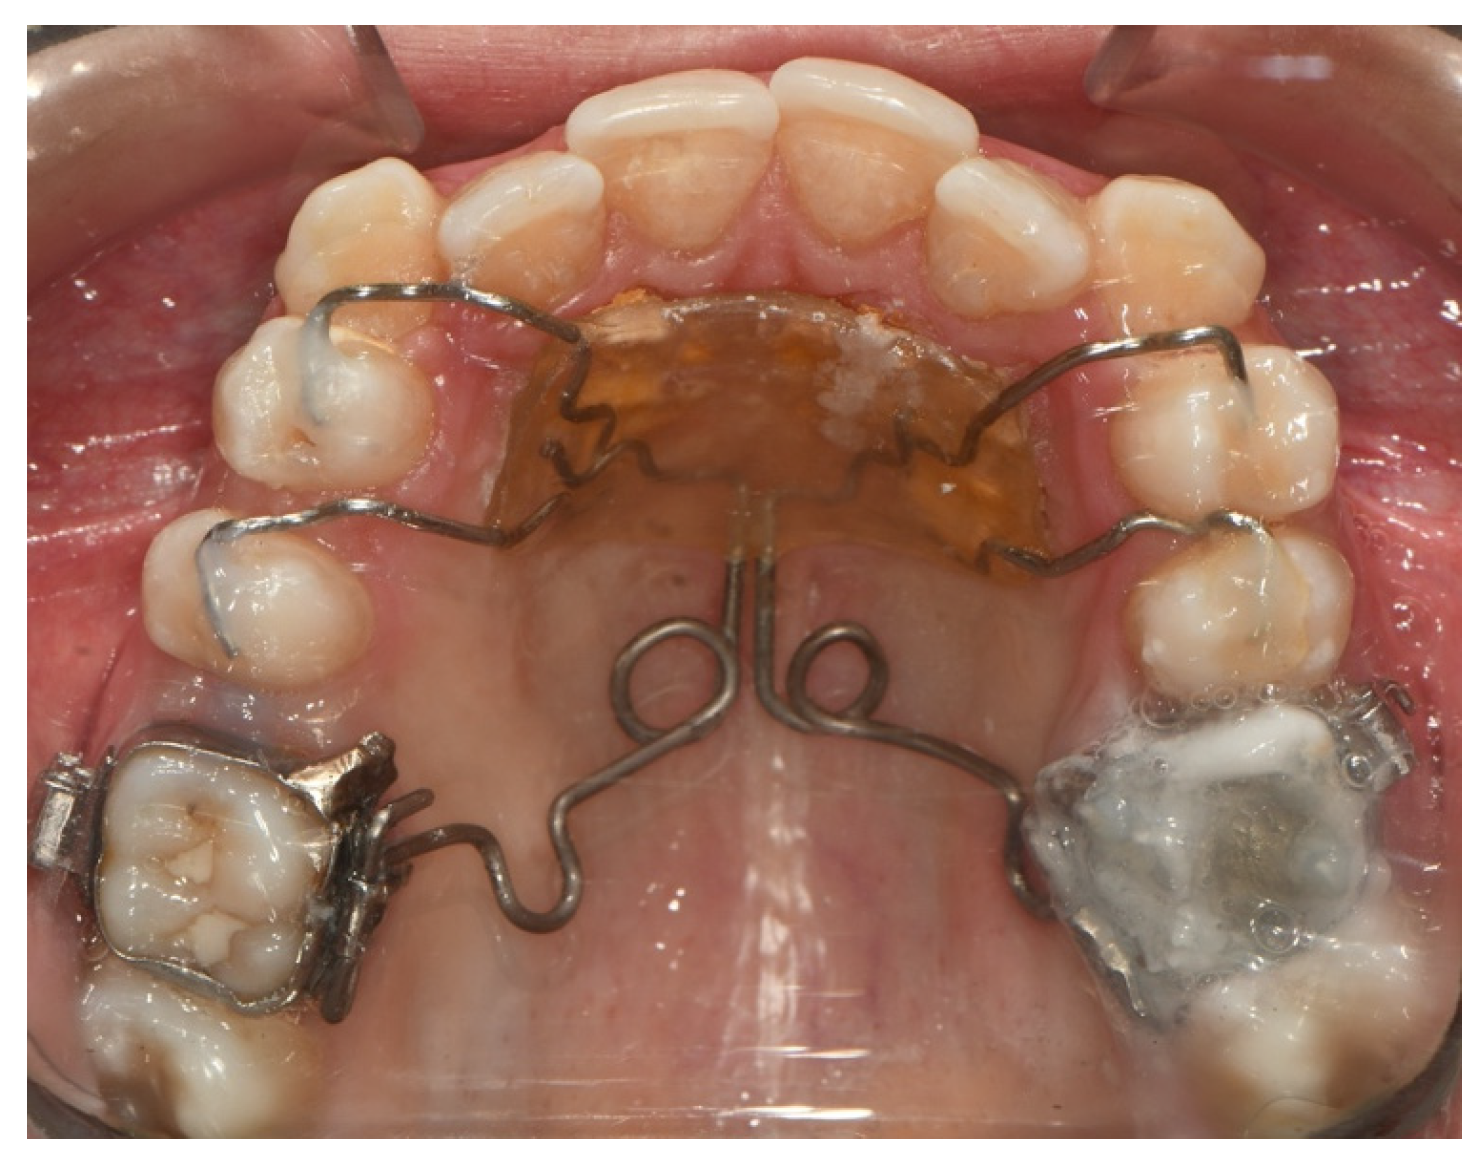

4.1.13. Pendulum Appliance

Modified Pendulum Appliance

- Kircelli, B.H.; Pektaş, Z.O.; Kircelli, C. Maxillary molar distalization with a bone-anchored pendulum appliance. Angle Orthod. 2006, 76, 650–659. [Google Scholar]

- Escobar, S.A.; Tellez, P.A.; Moncada, C.A.; Villegas, C.A.; Latorre, C.M.; Oberti, G. Distalization of maxillary molars with the bone-supported pendulum: A clinical study. Am. J. Orthod. Dentofac. Orthop. 2007, 131, 545–549. [Google Scholar] [CrossRef]